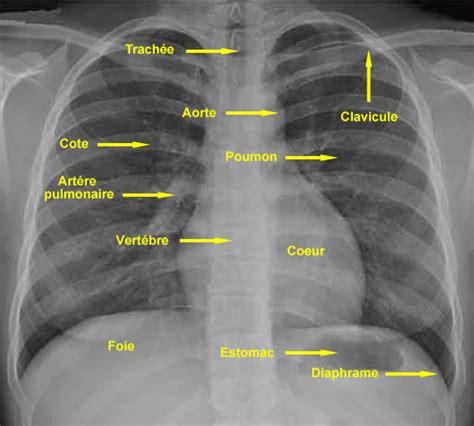

La radiographie thoracique, en particulier l'incidence de face, permet d'évaluer la taille et la forme du cœur, ainsi que les contours des gros vaisseaux qui l'entourent. Une dilatation des cavités cardiaques est l'une des causes principales de modifications de la silhouette cardiaque. Cette dilatation se traduit souvent par une cardiomégalie, définie par un index cardio-thoracique supérieur à 0,5, une mesure qui compare la largeur maximale du cœur à la largeur maximale du thorax.

L'analyse détaillée des différents arcs de la silhouette cardiaque permet de localiser précisément les anomalies. Par exemple, une dilatation de l'oreillette droite se manifeste par un élargissement de l'arc inférieur droit, lui conférant un aspect plus convexe. De même, une dilatation du ventricule droit entraîne une saillie de l'arc inférieur gauche, lui donnant un aspect arrondi et surélevé au niveau de la pointe. Une dilatation importante de l'oreillette gauche peut provoquer un aspect de double contour de l'arc inférieur droit et, de manière significative pour notre sujet, une saillie de l'arc moyen gauche. Enfin, une dilatation du ventricule gauche se traduit par une saillie de l'arc inférieur gauche qui tend à se rapprocher de la partie latérale du thorax.

L'arc moyen gauche, dans une radiographie thoracique normale, est principalement formé par la crosse aortique et l'artère pulmonaire. Lorsque cet arc présente une saillie anormale, cela peut indiquer plusieurs pathologies. La dilatation de l'artère pulmonaire est une cause fréquente de cette saillie. L'artère pulmonaire est le vaisseau qui transporte le sang désoxygéné du ventricule droit vers les poumons. Sa dilatation peut être le signe d'une hypertension pulmonaire, une condition où la pression sanguine dans les artères pulmonaires est anormalement élevée.

Le médiastin, la région centrale du thorax située entre les deux poumons, abrite des structures vitales telles que le cœur, l'aorte, la trachée, l'œsophage et les ganglions lymphatiques. Les contours médiastinaux, visibles sur les radiographies de thorax, fournissent des informations précieuses sur l'état de ces organes. À droite, l'arc supérieur correspond au tronc veineux brachio-céphalique droit, l'arc moyen à la veine cave supérieure, et l'arc inférieur à l'atrium droit et, dans une moindre mesure, à la veine cave inférieure. Le hile pulmonaire gauche est physiologiquement situé légèrement plus haut que le hile droit.